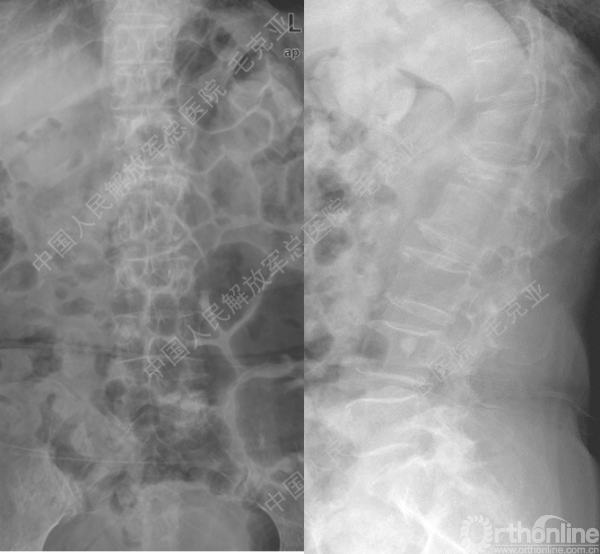

导语:随着社会老龄化的不断加速,骨质疏松性椎体压缩骨折作为一种普遍存在的老年骨科疾病已经成为现今骨科界的一个热点话题。传统的保守疗法治疗效果不佳,而现有的椎体增强技术又具有多种风险和缺陷。针对这种现状,中国人民解放军总医院毛克亚教授提供了一种新的解决方法。